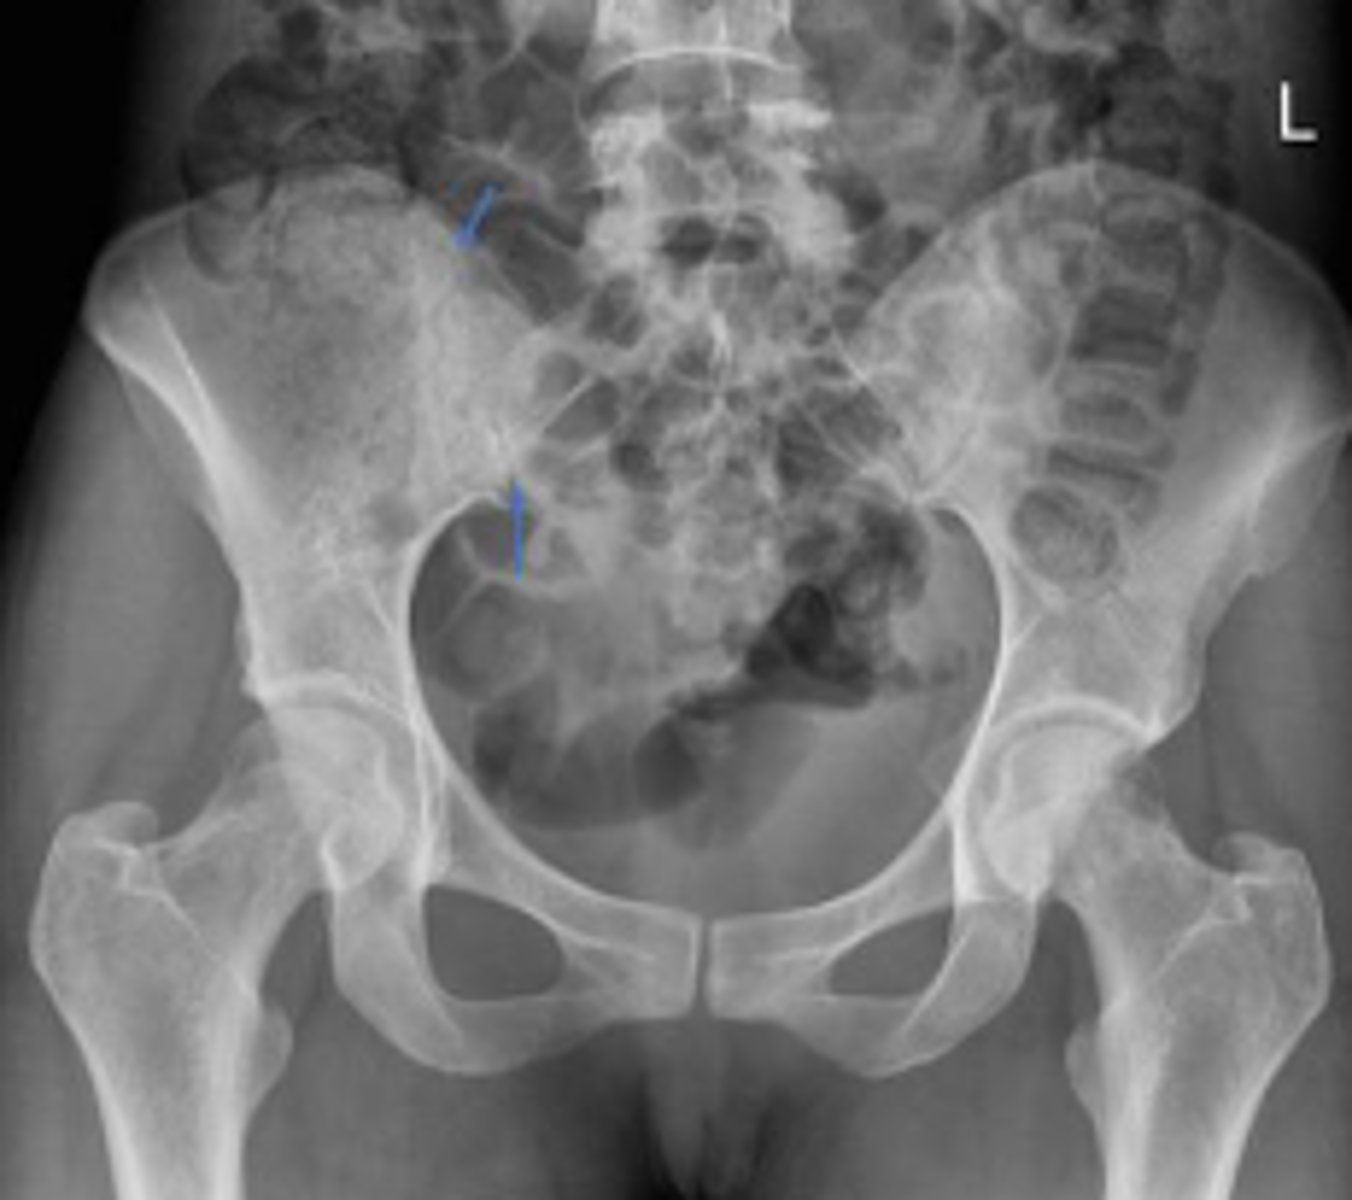

Phleboliths

What are the arrows pointing to?

L4/L5 IVD space

Which IVD space is indicated by the arrows?